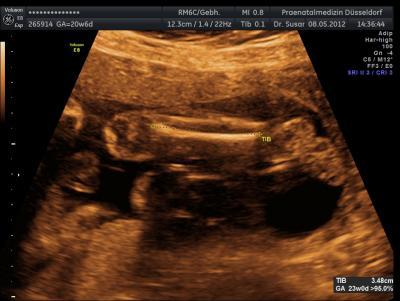

Gestern hatte ich total vergessen euch ein paar Bilder von meinem Würmchen zu zeigen.Wir haben zwar keines vom Gesicht bekommen,aber andere schöne waren dabei. Wollte euch mal ein paar zeigen :)

Sind das immer die Beine bzw.Arme??? Hast duauch ein Gewicht und eine Maße bekommen??

Das sind die Beine. Also mein Kleiner war gestern 27 cm groß und knapp 500 gramm schwer. Nach dem Kopfumfang hab ich gar nicht gefragt vor Aufregung Da müsste ich noch mal in den Befund schauen, da steht es mit Sicherheit drin. Leider hat er wie gesagt seinen Kopf + Oberkörper immer schön weg gedreht wenn die Ärztin ein Foto knipsen wollte. Trotz rütteln und schütteln am Bauch. Zum Dank bekam ich nur ein paar saftige Tritte